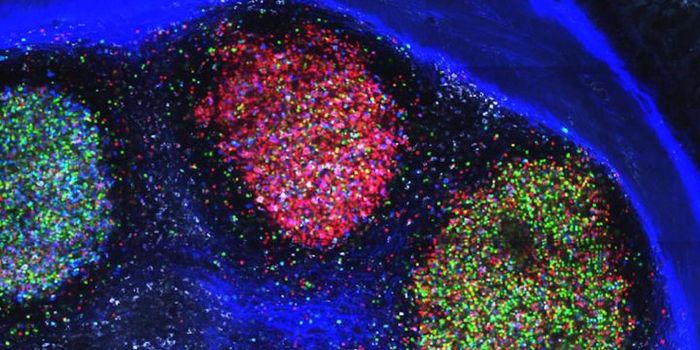

DEC 06, 2021Cell & Molecular BiologyTo meet the demands of cutting-edge biomedical research, NanoString have launched a spatial transcriptomics platform cal ...